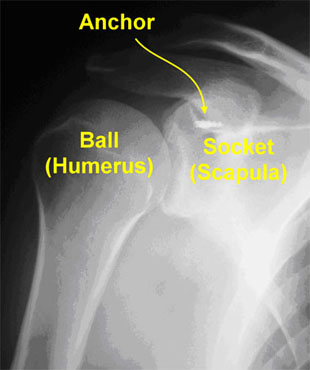

The shoulder is a ball and socket joint, similar to a golf ball on a tee. A rim of tissue called the labrum surrounds the socket like a bumper on a pool table.

Several muscles in the shoulder and arm insert on the ball and socket. For example, the biceps muscle in the arm is anchored on top of the labrum.

The torn tissue is stitched back to the bone. By stitching the torn tissue back to the bone, the SLAP tear can heal in its proper location. The stitches are held in the bone with anchors that are drilled into the bone.

Shoulder X-Ray showing anchors in bone for SLAP repair